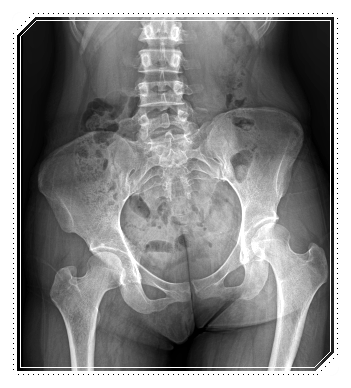

O자 다리를 단순히 ‘다리가 휘었다’는 한 가지 기준으로만 보지 않습니다.

다리의 휜 모양, 발 회전 각도, 다리 각도와 정렬, 측면에서의 휨 형태 등 다양한 요소를 세밀하게 나눠 살펴야 합니다.

- 무릎 아래쪽만 휜 경우와 허벅지부터 휜 경우

몸의 축이 틀어지면 무릎, 골반, 척추까지 영향을 주는 전신 정렬 문제로 이어집니다.